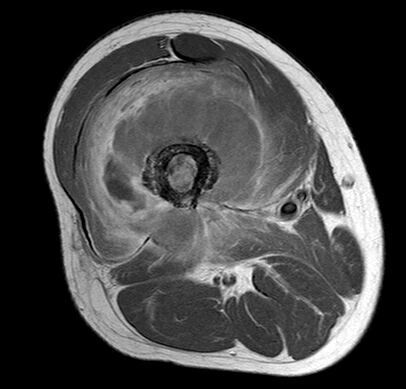

瘤软骨

瘤软骨为肿瘤细胞产生的软骨基质,多来源于软骨类肿瘤,或内有化生瘤软骨成分的其他肿瘤如成软骨型骨肉瘤。瘤软骨为软组织密度,未钙化时,主要通过 MRI 检查显示。由于瘤软骨多由富含水分及粘多糖的透明软骨构成,故 T1WI 呈偏低信号,T2WI 或 PDWI 呈明显高信号,被低信号的纤维间隔分开呈分叶状(图 24、图 25a-b),增强扫描多呈不均匀分隔状强化(图 25c),主要是纤维间隔强化,瘤软骨强化不明显之故。

图 24.瘤软骨:内生软骨瘤

图 25.瘤软骨:内生软骨瘤